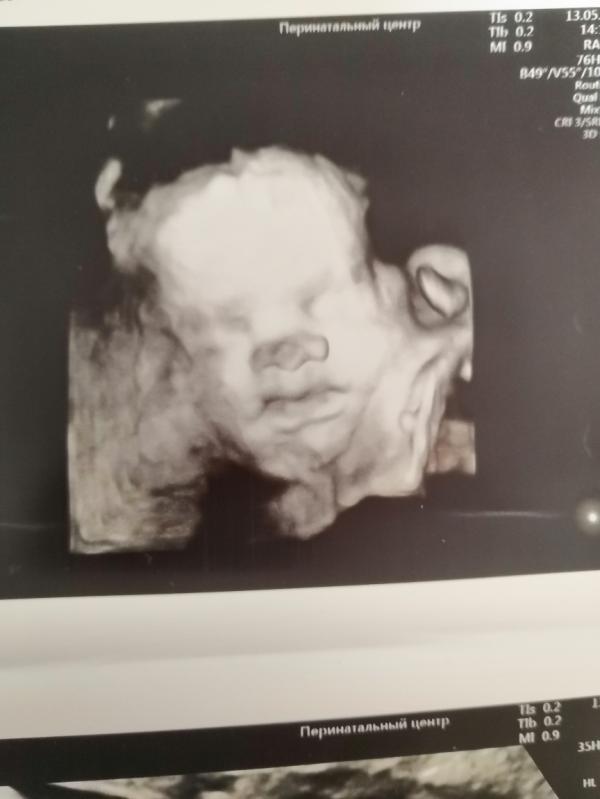

А это сынок в 28,1😍Вес 1172 г

Животик почти на неделю меньше срока, а так все замечательно. Как истинный пацан-сидит на корточках 😂